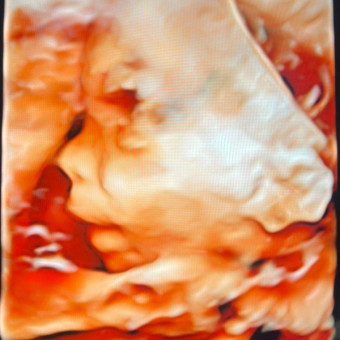

Baby B

Mariana & Sean Brady

Hopatcong, NJ

August 12, 2024

We can’t wait to live this new chapter of our lives! Briana Batista Brady.